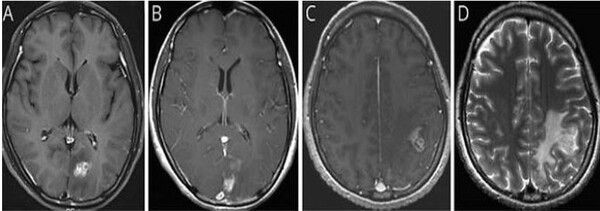

[예시] (A) 초기 뇌 MRI에서 좌측 후두엽에 조영증강된 종괴가 관찰됨 (B) 3개월 뒤 시행한 뇌 MRI에서 좌측 후두엽의 종괴가 사라짐 (C) 8개월 뒤 시행한 뇌 MRI에서 좌측 두정엽에 새롭게 조영증강된 종괴가 발견됨 (D) 좌측 두정엽 종괴 주변에 심한 뇌부종이 동반된 모습이 확인됐다. / 서울대병원제공

이번 연구는 서울대병원에 내원한 40대 여성 환자를 대상으로 이루어졌다. 환자는 심한 두통과 구토 증세로 병원을 방문했으며, 초기 뇌 MRI에서 좌측 후두엽에 불규칙하게 조영된 종양성 병변이 발견되어 뇌종양이 의심됐다. 의료진은 수술을 권유했지만, 환자는 증상이 일시적으로 호전되자 치료를 거부하고 퇴원했다.

환자는 7개월 후 다시 극심한 두통과 전신 발작으로 병원을 방문했다. 후속 MRI에서 병변이 좌측 후두엽에서 좌측 두정엽으로 이동한 것이 확인됐고, 이 병변 이동은 스파르가눔증의 대표적인 진단 단서가 됐다. 환자는 과거 오염된 연못물을 마시고, 날생선 및 익히지 않은 야생 동물 고기를 섭취한 이력이 있어 의료진은 기생충 감염을 염두에 두고 ELISA 검사와 정위적 생검을 시행했다.